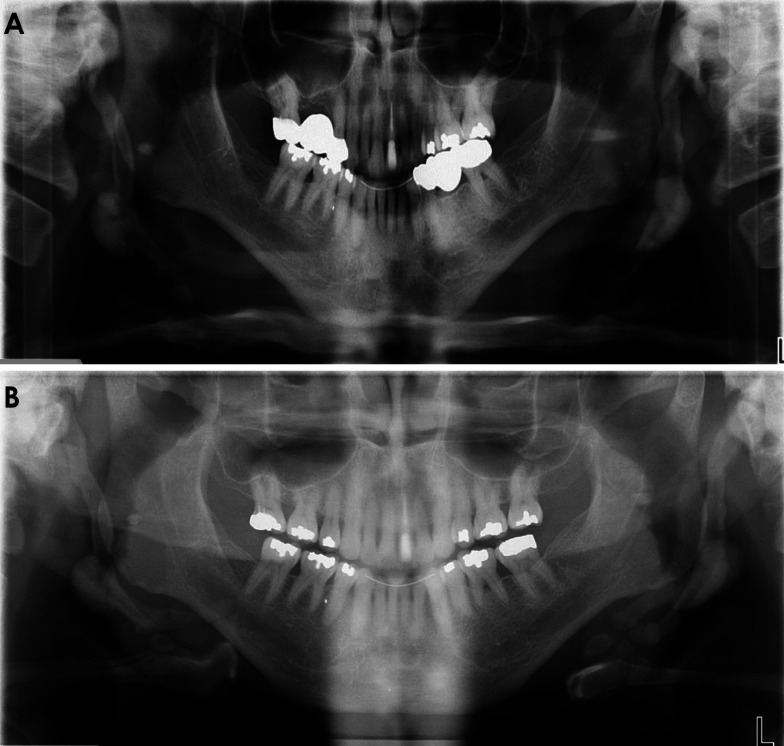

A 54-year-old male patient presented for a periodic check-up at the dental clinic. A panoramic radiograph showed bilateral ossification of the stylohyoid ligament with an oval radiopacity on the right side. Cone-beam computed tomography revealed a well-defined, homogenous hyperdense entity from the lower third of the ossified stylohyoid ligament on the right side. The differential diagnosis of osteoma on the stylohyoid chain includes Eagle syndrome and benign tumors of the stylohyoid chain and adjacent structures. Osteoma rarely manifests in the neck. Even more infrequent are tumors originating from the stylohyoid chain, with only a single documented case of osteoma reported in the literature in 1993. Due to the asymptomatic status, no surgical intervention was advised, and the case would be monitored periodically. This case report describes the details of an osteoma that emerged from the stylohyoid chain, marking it as the second recorded occurrence of this highly rare condition.